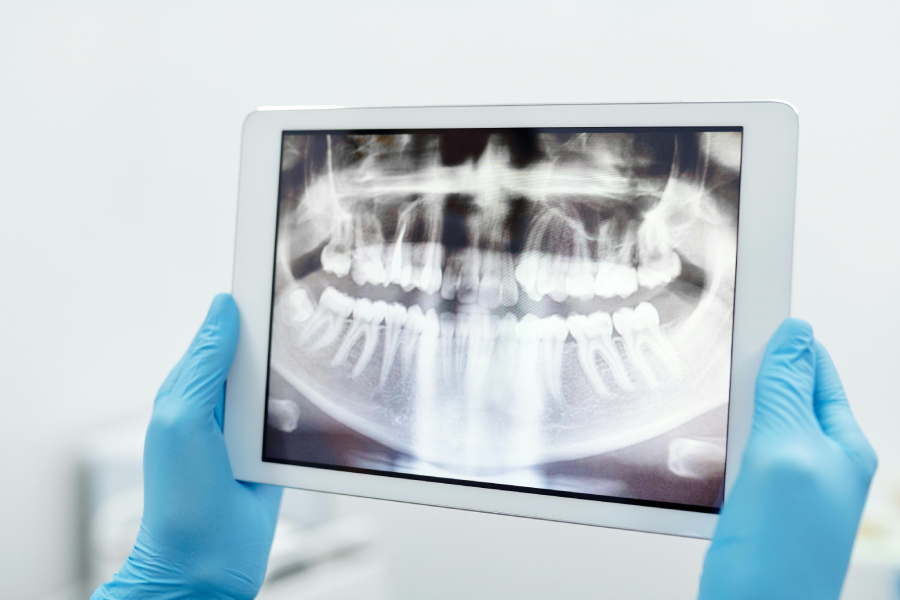

Η πανοραμική οδοντιατρική ακτινογραφία ή ορθοπαντομογραφία είναι μία ακτινογραφία που παρέχει μία πλήρη εικόνα της στοματικής κοιλότητας, καλύπτοντας τις δύο γνάθους και τα δόντια σε μία ενιαία απεικόνιση.

Η συγκεκριμένη εξέταση χρησιμοποιείται για να εκτιμήσει τη γενική κατάσταση των δοντιών, των γνάθων και των γύρω ιστών, προσφέροντας πολύτιμες πληροφορίες για την υγεία της στοματικής κοιλότητας. Η εξέταση είναι μη επεμβατική, ανώδυνη και γρήγορη, και συνήθως απαιτεί λιγότερο από 5 λεπτά για να ολοκληρωθεί.